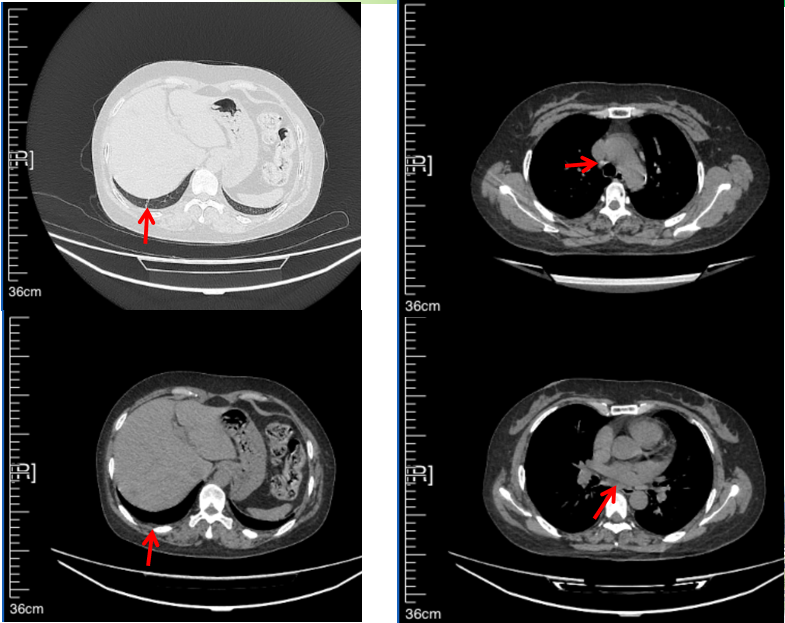

56岁,女性,无吸烟史饮酒史,既往体健。2023年02月患者体检发现肺占位性病变,胸部增强CT:右肺下叶后基底段结节;右侧锁骨上及纵隔内多发淋巴结肿大。PET-CT:右肺下叶周围型肺癌可能性大;1R、2L、3P、4R、4L及7组淋巴结转移可能性大。2023年02月就诊于本院胸外科行超声胃镜下纵隔肿物穿刺活检术,病理:结合免疫组化,符合肺腺癌。行NGS基因检测:EML4:exon20-ALK:exon20融合。PD-L1(克隆号22C3)TPS=55%。

临床诊断:右肺下叶恶性肿瘤cT1bN3M0,IIIB(第9版分期),纵隔淋巴结继发恶性肿瘤,锁骨上淋巴肿继发恶性肿瘤

治疗经过:2023年3月27日始行恩沙替尼靶向治疗至今,最佳疗效为PR,末次评效为维持PR。期间出现轻度肝功能异常(DILI 1级),对症处理后好转。截止目前PFS为26个月。

2023年2月20日基线检查

2024年6月复查PR(最佳疗效)

2024年12月复查维持PR

2025年3月复查维持PR